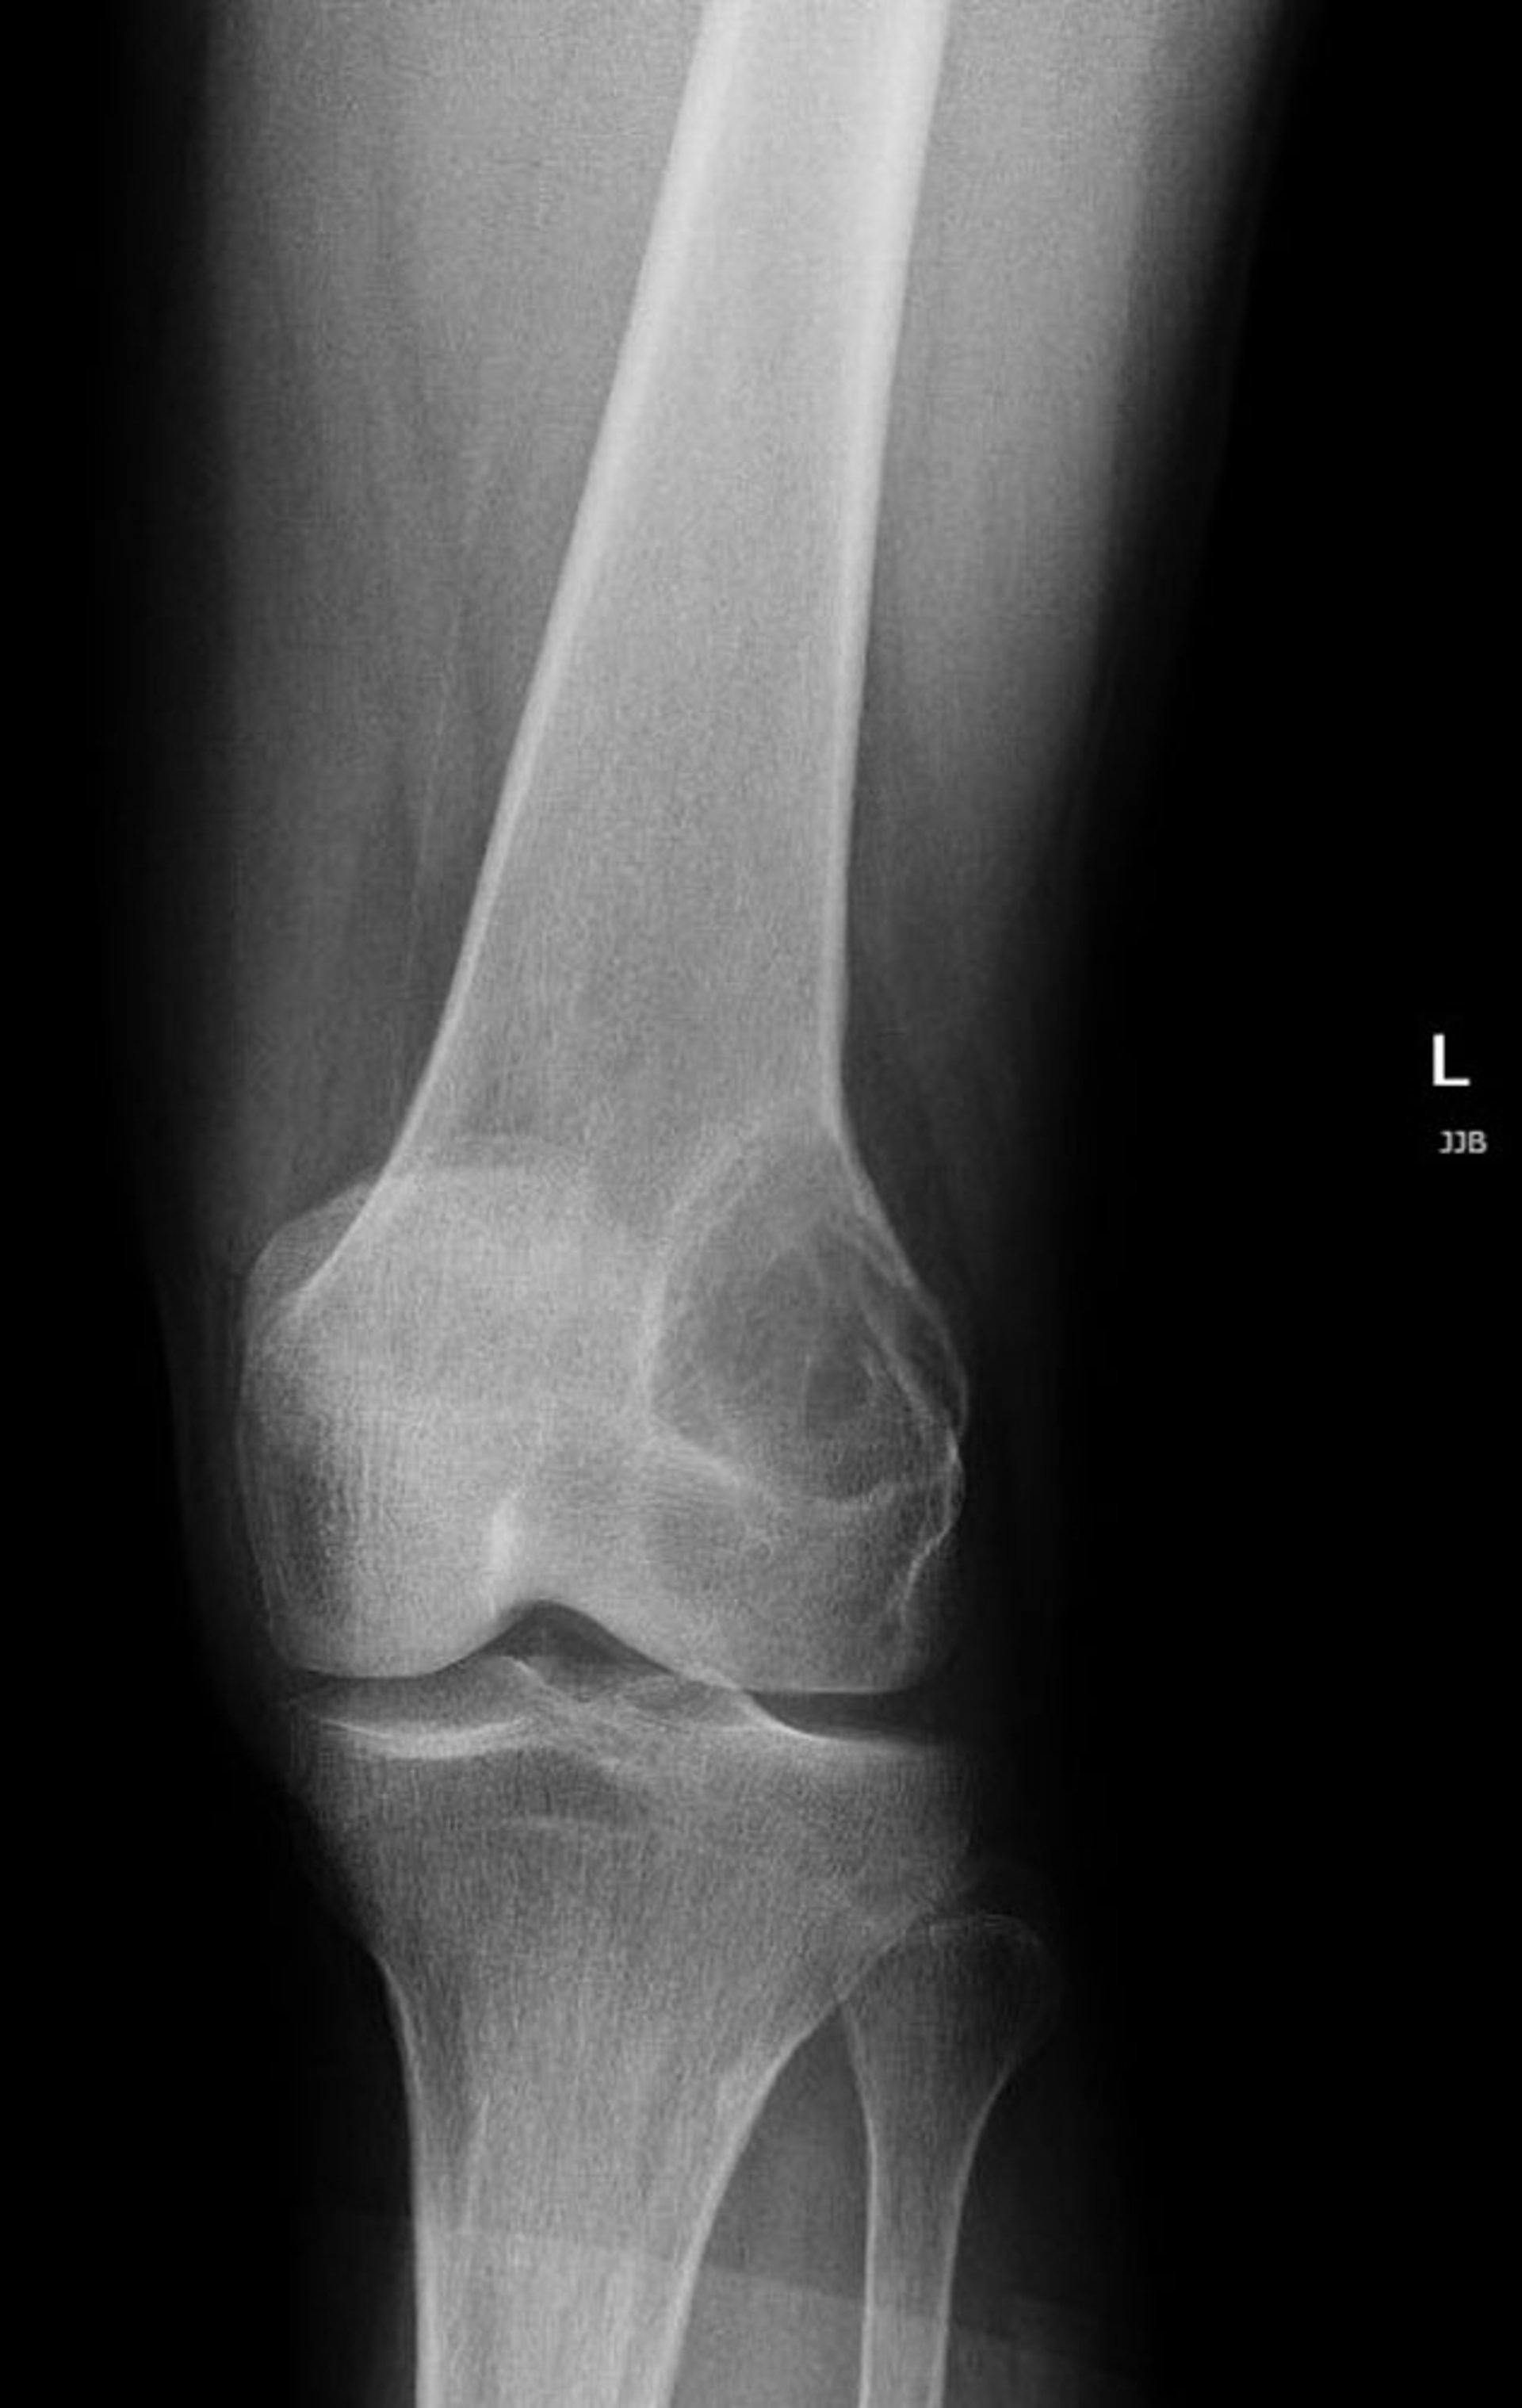

膝关节的X光片显示膝盖上方股骨远端外侧有一处透亮病变,这是骨巨细胞瘤的典型特征。

Image courtesy of Lukas Nystrom, MD.